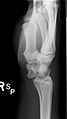

Perilunar dislocation as seen on x-ray.

The lunate bone is the most frequently dislocated carpal bone.